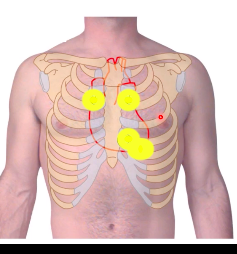

which valves are where? xox

A = aortic valve P = pulmonary trunk valve T = tricuspid valve M = mitral valve

where do u take a thoracentesis (a procedure to remove fluid or air from around the lungs) from?

below the level of the lung

mid-axillary line - 9th intercostal space in the inferior intercostal space

where would you do a thoracostomy (Thoracostomy is a minimally invasive procedure in which a doctor inserts a thin plastic tube into the pleural space — the area between the chest wall and lungs)

thoracostomy: mid-axillary line, inbetween 4th and 5th intercostal space

needle decompression: mid clavicular line, middle of 2nd / 3rd intercostal space